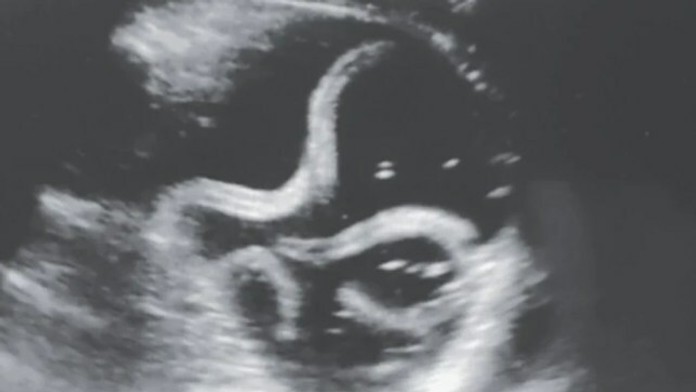

Nepríjemný nález ultrazvukom: Mužovi žili v žalúdku červy

Zdroj: Chaurasia & Bhoi, NEJM, 2020

Mladý 20-ročný muž z Indie bol zhrozený, keď zistil, čo mu spôsobuje nepríjemné bolesti v bruchu. Ultrazvuk ukázal, že mu v žalúdku žili parazitné červy, ktoré si z mladíka spravili svojho hostiteľa, uviedol portál metro.co.uk.

Podľa všetkého išlo o hlístovce (nemathelminthes), ktoré môžu dorastať do dĺžky niekoľkých centimetrov. Mužovi spôsobovali bolesti, hnačky a zvracanie.

Lekári podali mužovi antiparazitnú liečbu za pomoci lieku nazývaného albendazol.